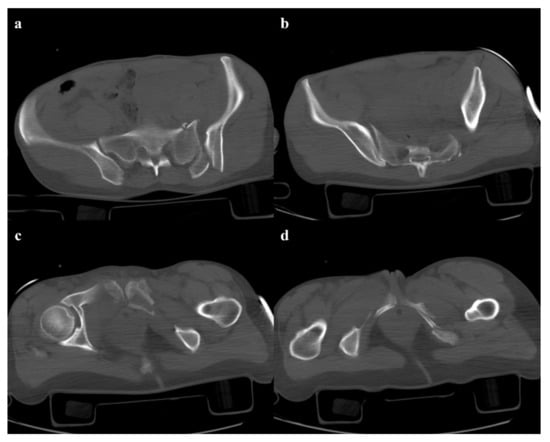

Figure 3. Lateral compression fracture, type 3. Axial CT images show the fracture of the iliac and sacral wings on the left side (a), anterior widening of the right sacroiliac joint (b), and fracture of bilateral pubic branches (c,d).

• Grade 3: the lateral compression force is associated with a contralateral anteroposterior compression force, with an external rotation of the contralateral hemipelvis (“windswept pelvis”). Grade 1 or grade 2 lateral compression injuries are associated with a contralateral sacroiliac joint diastasis (Figure 3). Lateral compression grade 3 injuries have a multidirectional instability and require a stable internal fixation [3]. In these lesions, an adjunctive temporary external fixation is useful [3].